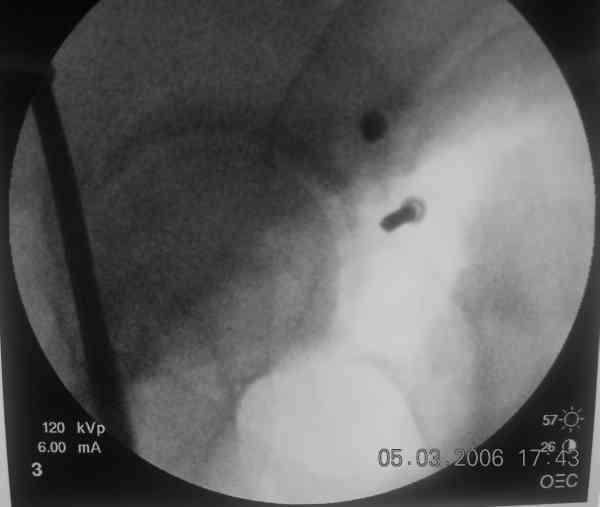

the case that I found is a 20yo male, MCC. his AP pelvis shows an interesting position of his bladder. it is pushed aside by a hematoma from SGA injury. we did a limited lateral window approach for the anterior column first, pt bumped up/supine. then closed and repositioned for KL. I could not find intra-op photos of cases when we did only a small incision for the AC screw (but they do exist!!). the lateral window is available for reduction assessment if a KL approach is being used. in the lateral position this window is available. the prone position definitely takes pressure off of the post column and facilitates reduction. in the lateral position a schantz pin in the ischial tub +/- bone hook in sciatic notch helps with PC reduction. the lateral position also gives better airway access for anesthesia. airway problems are rare, but prone position seems to be a bit more of a challenge to exchange the tube, or reintubate altogether. just something further to debate!